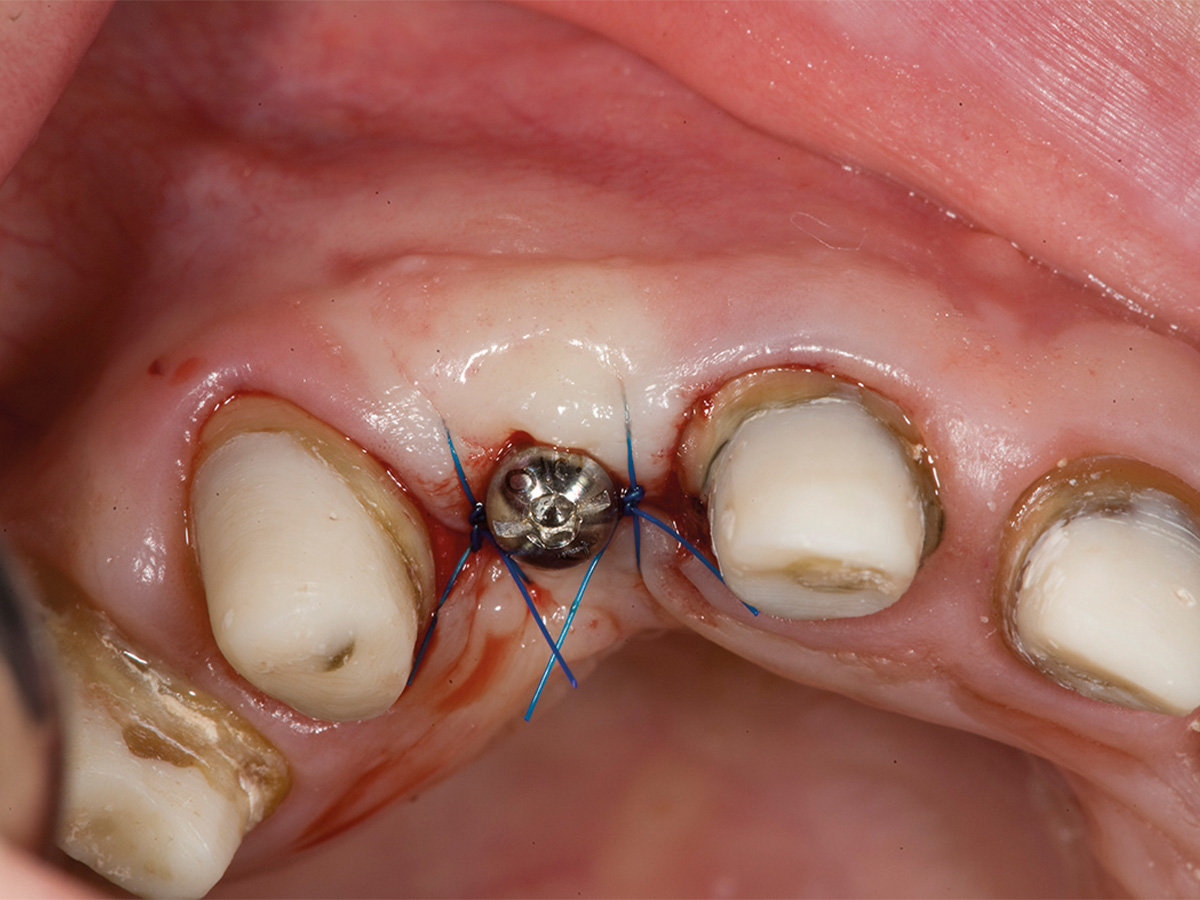

Abbildung 9

6 Monate post-OP nach Freilegung. Zu beachten ist der Alveolarkamm im Gegensatz zum Ausgangsbefund.